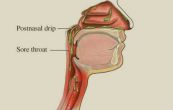

Hội chứng chảy dịch mũi sau là tình trạng cơ thể sản xuất nhiều chất nhầy ở mũi và cổ họng, khiến nó chảy xuống và tích tụ ở cổ họng. Cùng eLib.VN tìm hiểu bài viết dưới đây để hiểu rõ hơn nhé!